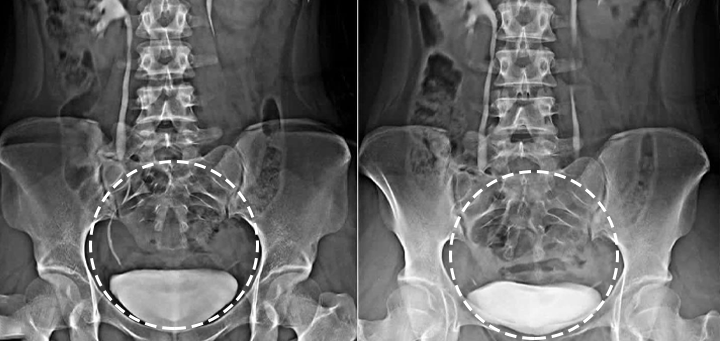

- Natural Anti-Inflammatory Effect: Effectively reduces inflammation and swelling associated with prostatitis and BPH.

- Relieves Symptoms of BPH and Prostatitis: Helps alleviate common symptoms such as difficulty urinating, frequent urination, and urgency.